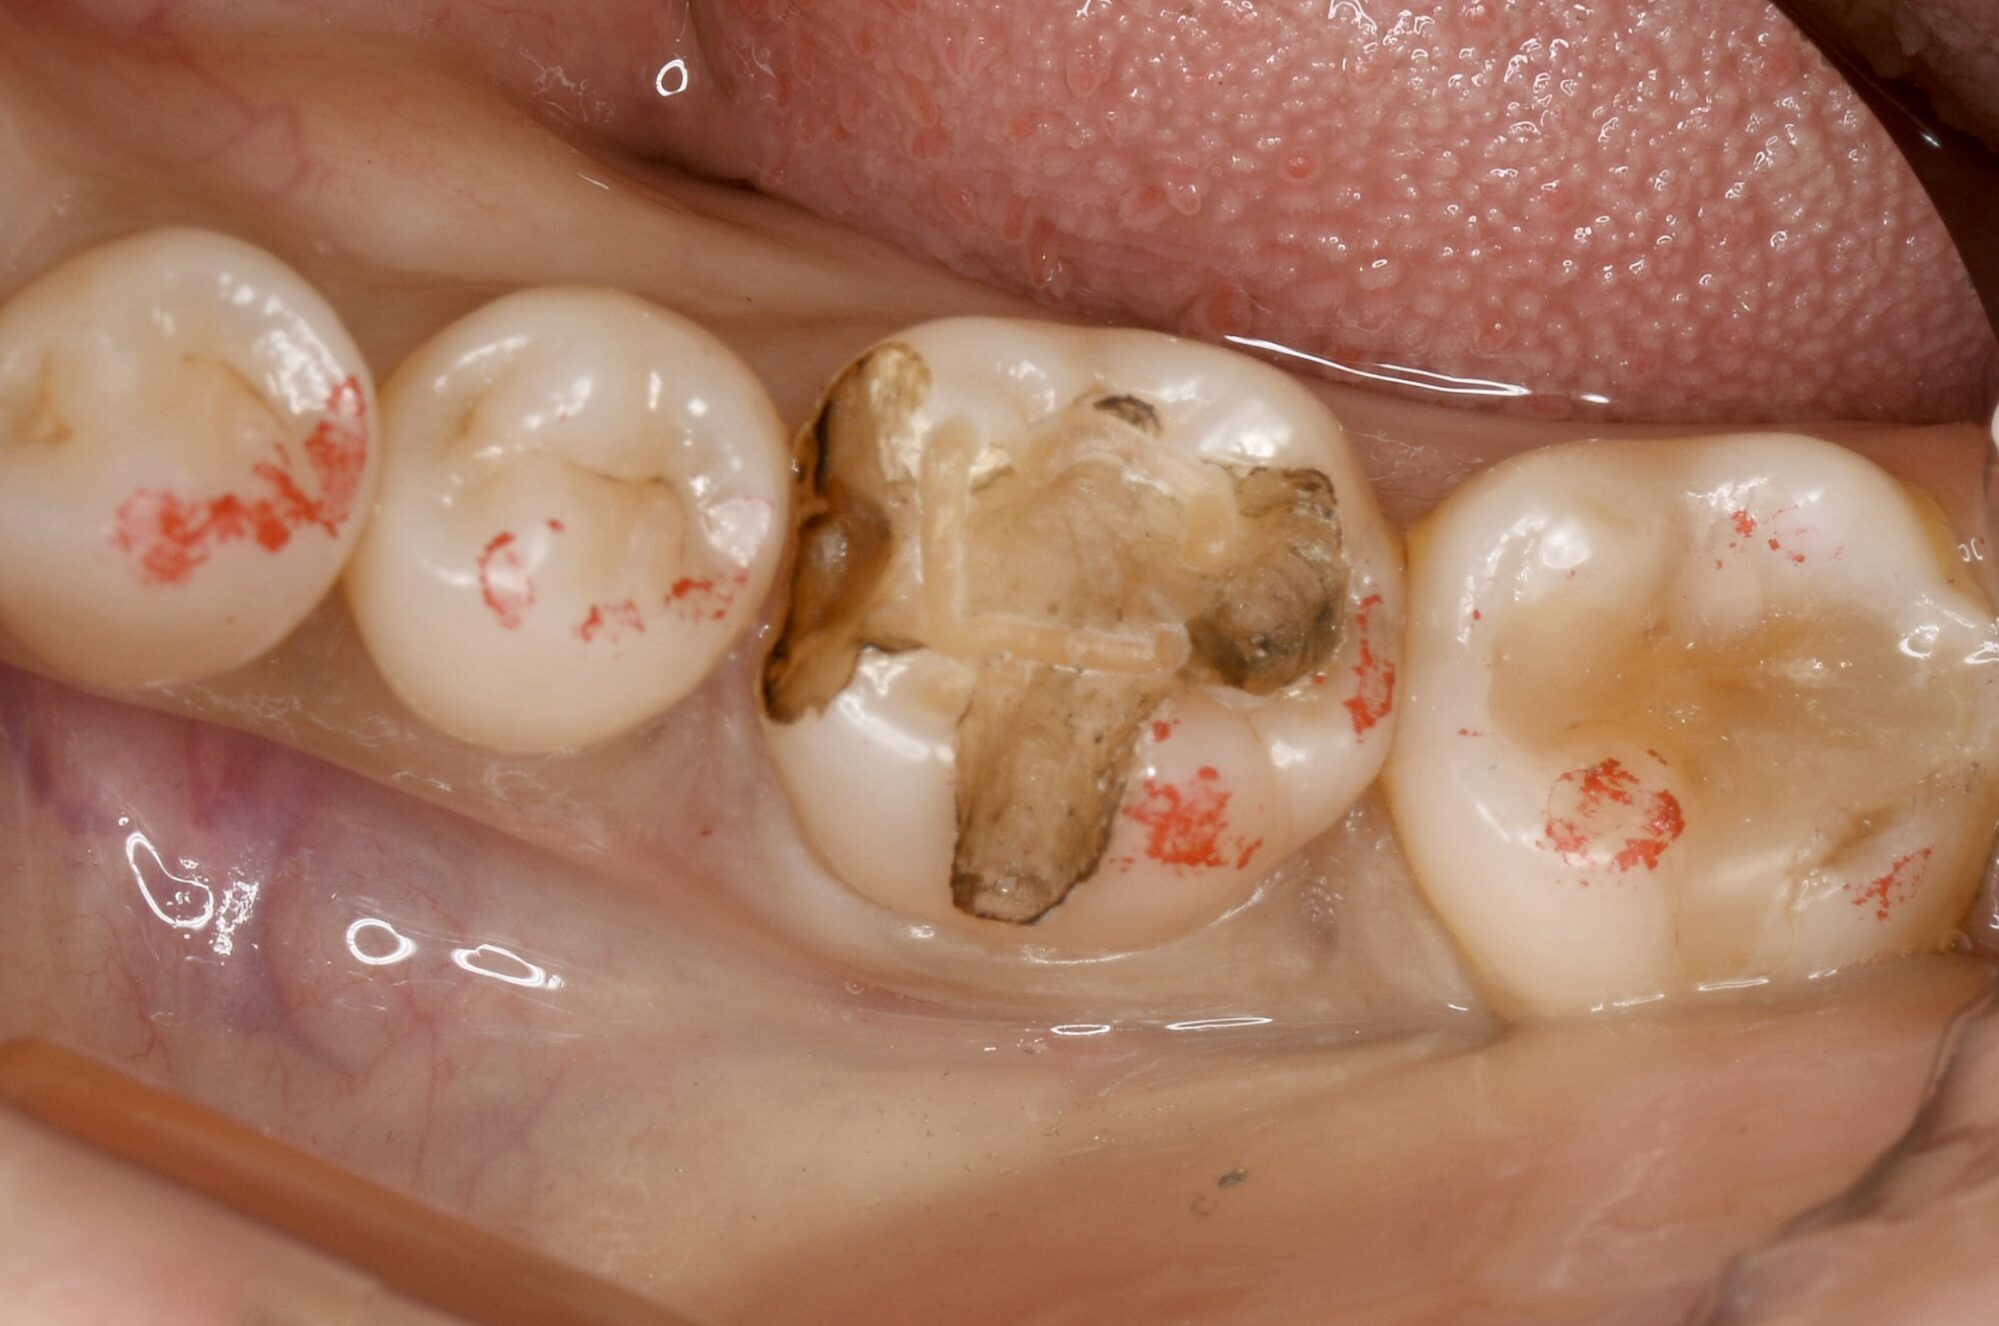

対象となる下の奥歯には、過去に治療した銀歯(メタルインレー)が装着されていましたが、銀歯と歯の境目にわずかな隙間が生じていました。

レントゲンおよび視診の結果、「インレー下カリエス(二次むし歯)」と診断しました。銀歯の中でむし歯が再発している状態です。

このまま放置すると神経まで達する恐れがあったため、銀歯を外してむし歯を取り除き、新しい詰め物で修復する必要があります。

銀歯を外すと、事前の診断通り内部にむし歯が広がっていました。

検知液(むし歯を染める薬)を使用し、健康な歯を削りすぎないよう配慮しながら、むし歯のみをきれいに除去し、セラミックが適合しやすいよう形を整えます。